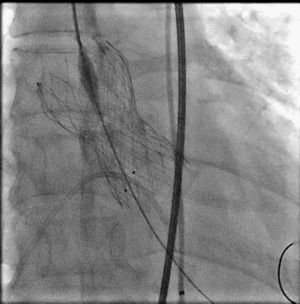

继续释放支架开始贴壁,此时血压还没完成下降,支架仍未完全开花

可以进行造影,观察位置

继续释放支架此时支架开花,血压下降到60以下时,可进行120-140起搏释放

建议此时释放速度无需过快,以便第一术者有间隙调整瓣膜位置,第三术者固定导丝

释放到血压开始回升停起博,造影,拉回辅路猪尾